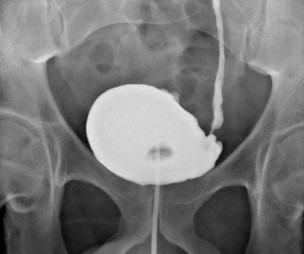

A drain was placed at the end of the procedure which was removed next day. Patient was discharged on day 2 after the procedure with catheter in-situ. Cystogram performed 3 weeks later showed no leak and had successful the trial without catheter.

Figure 3: Cystogram showing no leakage with reflux of contrast over left JJ stent to the left kidney.